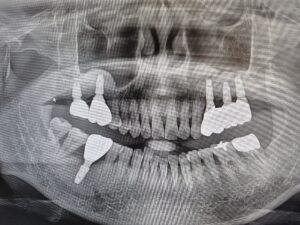

충분한 뼈가 있어야 임플란트가

단단히 고정되고 오래 사용할 수 있기 때문에,

뼈 이식과 상악동거상술은

성공적인 임플란트 치료를 위한

핵심 과정이라 할 수 있습니다.

◆ 전 > 후 ◆